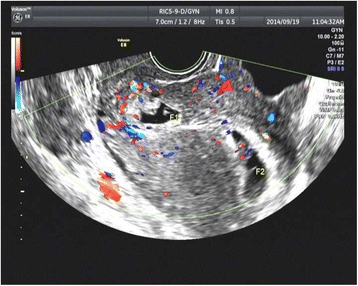

Methods: All the 12 cases were secondary infertility patients who had a history of Cesarean section and underwent IVF-ET in our reproductive center. All cases with CSP were diagnosed using transvaginal color Doppler sonography (TVS). Medical, surgical and expectant managements were implemented, and the management results were traced.

Conclusions: The Caesarean section and IVF-ET may increase the ratio of HCSP/CSP. TVS is a noninvasive and effective tool for use in diagnosing CSP. CSP should be carefully excluded in patients who have had a history of Caesarean section. Early diagnosis of CSP in the first trimester may contribute towards the preservation of uterus as well as intrauterine pregnancy (IUP) in HCSP.